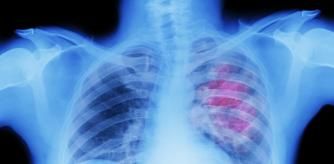

El grupo de Melero Bermejo descubrió que esos neutrófilos atraídos por la interleucina-8 penetran en el tumor y, cuando están presentes en cantidades suficientemente elevadas, los pacientes no suelen responder a la inmunoterapia. También vieron que ese 'perfume' que usa el tumor era capaz de inducir un curioso mecanismo de los neutrófilos que, habitualmente, nos protege de infecciones pero que se sabe juega a favor del cáncer. Ante una infección,los neutrófilos lanzan el ADN de su núcleo y forman redes que atrapan al patógeno y lo eliminan, gracias a que están recubiertas de proteínas tóxicas para bacterias y hongos. En los tumores, los neutrófilos también lanzan esas redes pero, paradójicamente, protegen a las células tumorales del ataque de los linfocitos, que son las células de defensa a las que “despertamos” con la inmunoterapia para destruir tumores.